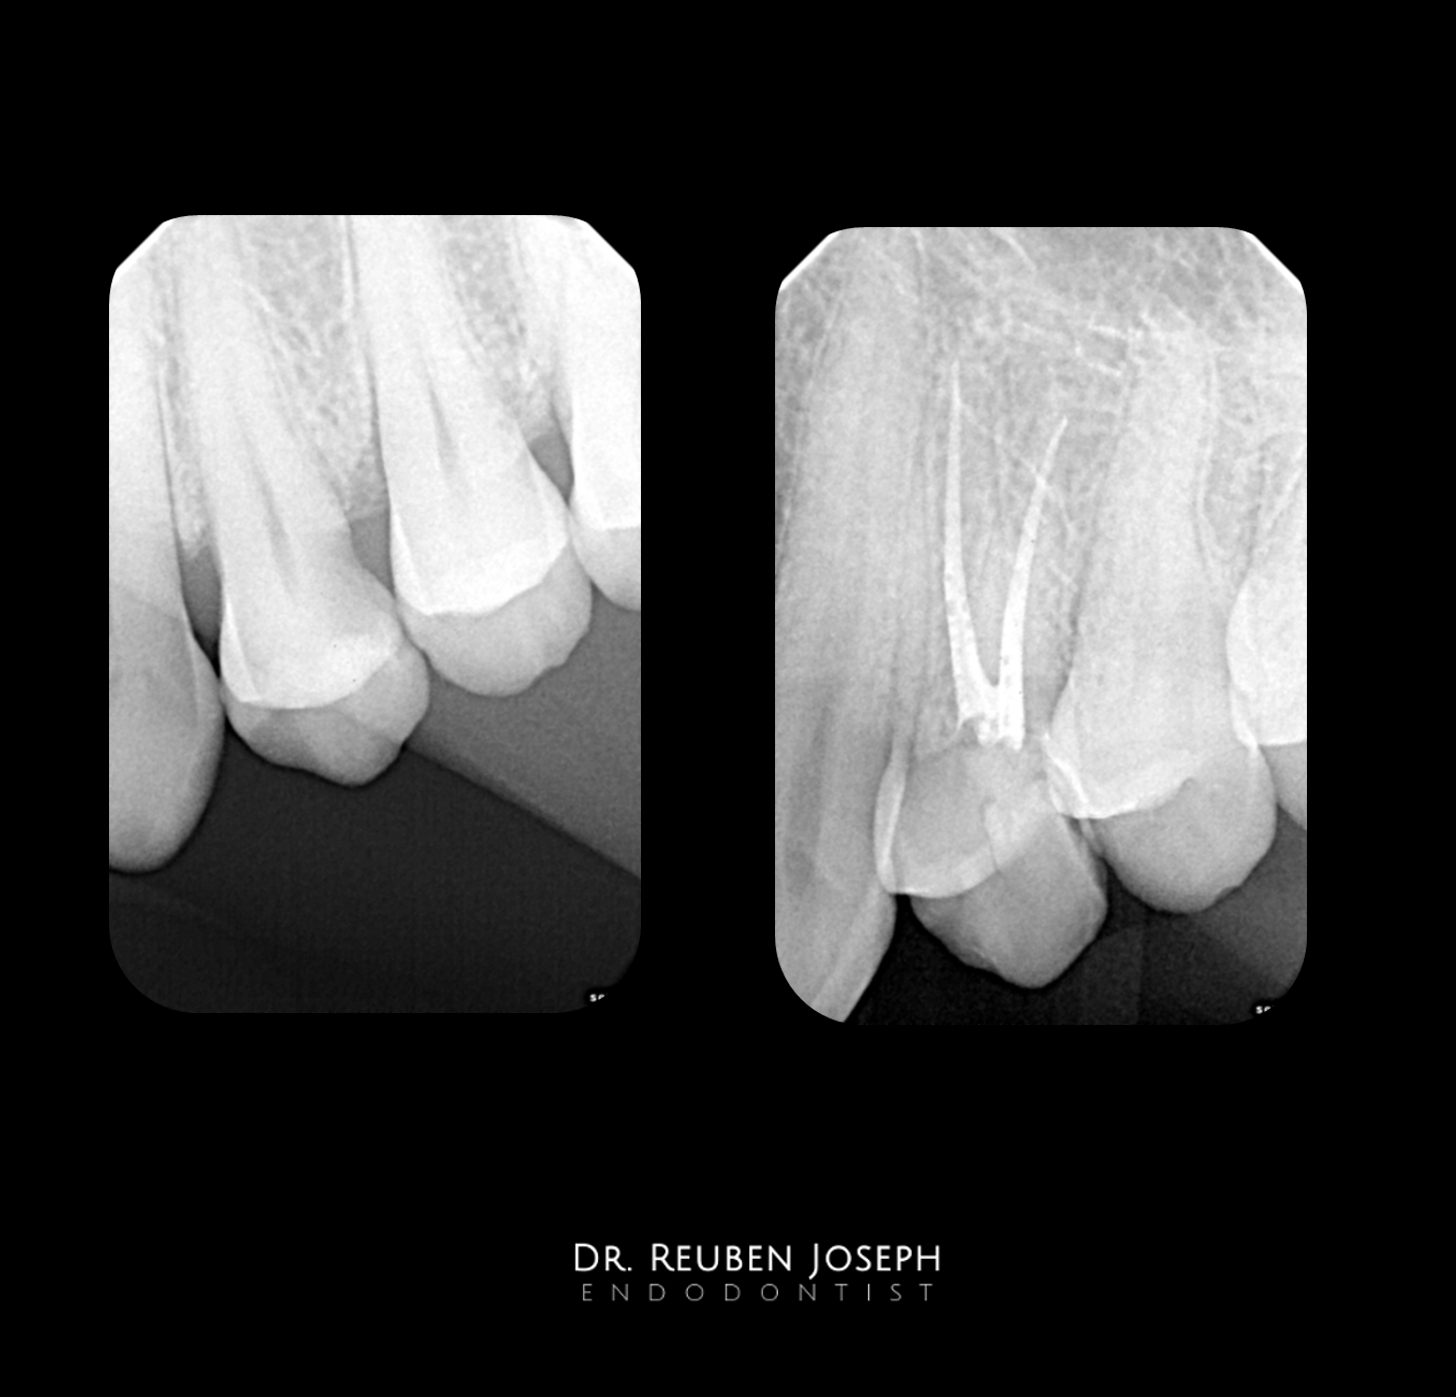

Nothing  special. A few premolars i got to treat recently with access cavity designs specific to what the clinical scenario demanded.

Case 2